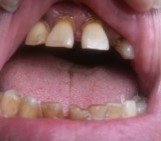

Болит сильно десна, опухла, когда дотрагиваешься — кровоточит. Что это может быть? Режется зуб или что-то с зубом? Что можно сделать?

Комментарий №161942

• Мой опыт подсказывает, что помимо воспаления десны и прорезывания зуба мудрости надо обратить внимание на возможную полость зуба в дальней половине восьмерки. Потому что цвет его такой, как-будто внутри развился кариес, поэтому может быть и десна в таком состоянии, а не только потому что зуб прорезывается.